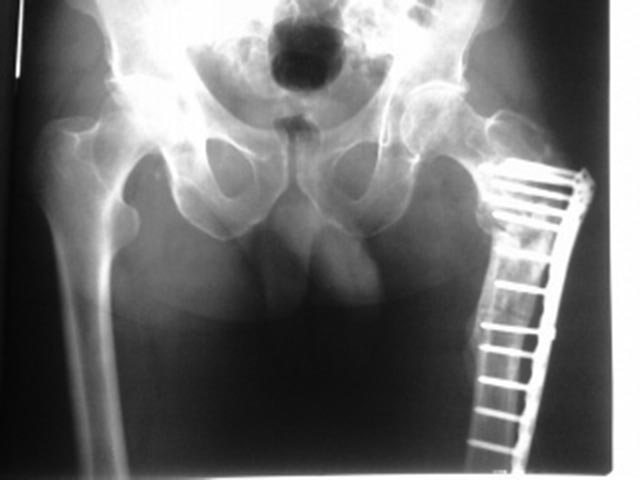

Мужчина 63 года, травма в феврале 2013 г. - перелом в/3 левой бедренной кости. В ЦРБ остеосинтез пластиной LCP. 17.06.2014 г. пластина удалена, стал отмечать боли, патологическую подвижность в бедре, укорочение левой нижней конечности на 4 см. 04.02.2015 г. в одном из учреждении г. Москвы произведена резекция ложного сустава, остеосинтез пластиной с пластикой Коллапаном. На сегодняшний момент беспокоят боли и патологическая подвижность в области верхней трети левого бедра, укорочение конечности на 4 см, передвигается при помощи костылей с нагрузкой на оперированную конечность. Рентгенограммы от 21.04.2015 г. и 16.08.2015 г.В отделении планируется: удаление пластины, остеотомия, восстановление ШДУ, фиксация стержнем. Вопрос: возможно ли выполнить операцию одномоментно или необходимо аппаратное удлинение бедра?

Да уж оба раза поработали "спецы". Снимок не очень что-то. По тому что рассмотреть удалось- вроде можно одномоментно. Стержень надо попрочнее, ШДУ чуть в вальгус. Удостовериться в отсутствии инфекции.

План вполне рациональный, но лучше бы увидеть схему того, что предполагается сделать. Где остеотомию, как будут располагаться отломки.

Чтобы ответить насчет длины - надо иметь что-то для измерений. Или снимок обеих нижникх конечеостей на одной пленке, либо можно уложить пациента на спину, выровнять таз, сделать снимки обоих проксимальных бедер на одной пленке, и обоих коленок на другой, не меняя положение пациента. Тогда будет хорошо видна разница длин, и будет понятнее, что получится от одной угловой коррекции.